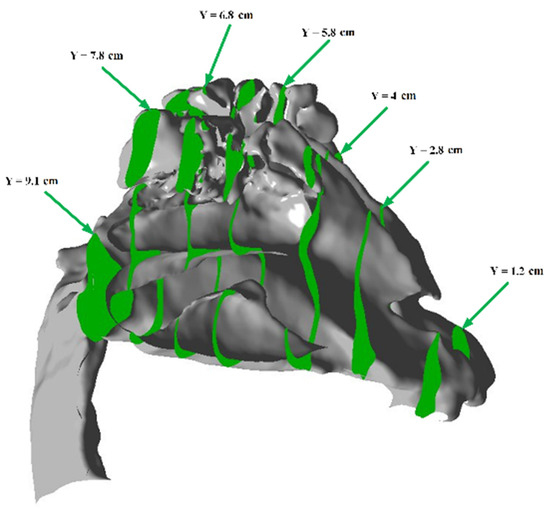

In this work, the average value of the flow rate was used as a parameter for adaptation. To determine the average speed and adjust the computational domain based on the geometry, auxiliary parallel planes were created. For example, in the case of the nasal cavity, sections were created in the OY plane, as shown in green in Figure 12.

In order to adapt the computational domain, a criterion similar to that of the nasal cavity, namely, the average velocity, was used. Due to the particular geometry of the lungs, parallel sections were created in the OZ plane, as shown schematically in Figure 16.

Figure 12. Auxiliary cutting planes perpendicular to the Y axis for adapting the computational mesh of the nasal cavity.